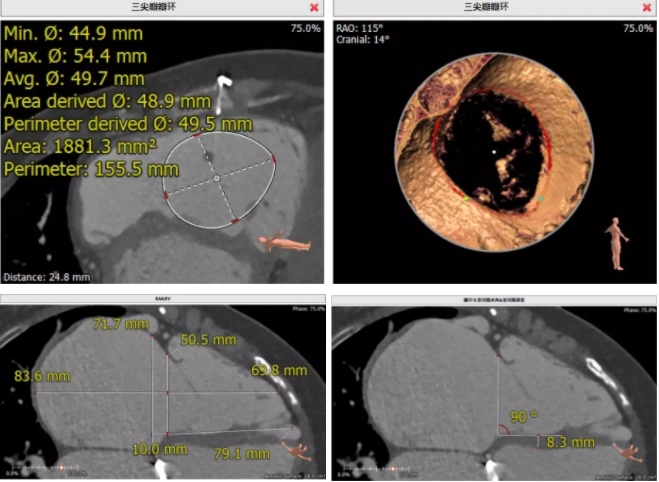

患者為68歲女性,14年前因“反復感冒、氣促”,檢查發現心臟瓣膜病,接受了“二尖瓣機械瓣置換術”。約5年前出現雙下肢水腫,活動后心累氣緊,心臟彩超提示:三尖瓣返流。近年來三尖瓣返流逐漸加重并伴有輕微黃疸、雙下肢水腫,雖長期服用利尿劑治療,但效果欠佳。郭惠明教授團隊結合病史、超聲及CT評估,考慮患者瓣膜置換術后,三尖瓣重度返流,再次開胸行體外循環手術風險高,經團隊整體評估,決定采用最適合患者的LuX-Valve三尖瓣置換系統行微創治療,根據測量結果選擇植入JS/TTVI-28-55型號的LuX-Valve瓣膜。

手術過程

經右側胸部微小切口,郭惠明教授團隊將輸送器經右房路徑,通過三尖瓣順利送入右心室,在DSA及超聲指導下精準地控制輸送系統釋放瓣膜,在超聲和DSA確認無瓣周漏及瓣膜系統穩定性良好后進行室間隔錨定。2例瓣膜置換過程均僅耗時10分鐘,術后超聲和造影顯示瓣膜位置形態良好,幾乎無返流。